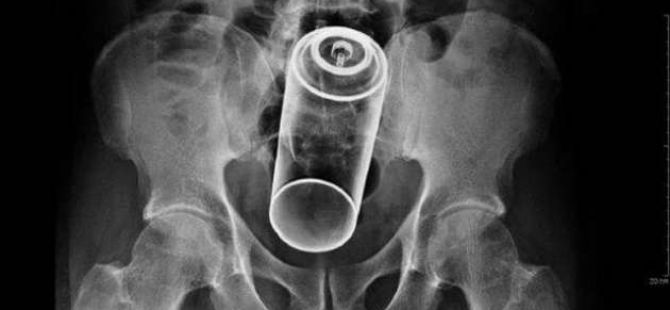

İÇİNDEKİ ŞEYE RÖNTGEN UZMANLARI ŞOK OLDU!

23 Ocak 2016 Cumartesi 17:38RÖNTGEN UZMANLARI ŞOK OLDU!

,Dünyada çekilen bu röntgenler hem röntgen uzmanlarını hemde görenleri şok ediyor...